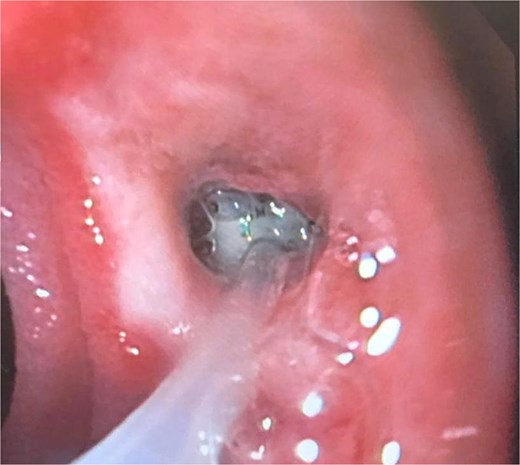

A 41-year-old female with a history of arterial hypertension underwent vertical sleeve gastrectomy for super obesity (BMI 52). She developed a complication of leakage in the cardia region, resulting in a gastropleural fistula and significant bacterial colonization, necessitating a left lobectomy. Persistent cough led to her referral to our department, where endoscopy revealed a 15-mm fistulous orifice. Previous endoscopic management with pigtails and endoscopic glue had failed, prompting initiation of EVAC therapy. Changes were made every 3–5 days, showing partial improvement. A treatment variant was applied by placing the sponge without suction (Fig. 4), promoting granulation tissue formation and enabling the patient to continue oral intake without lung leakage risk.

A cavity with an EVAC sponge is seen during endoscopic treatment.

This variant, leaving the sponge without a nasogastric tube and negative suction, aimed to manage the fistula while stimulating tissue granulation. Currently, although the fistula persists, she is tolerating oral intake with symptom improvement, and granulation tissue is present, suggesting that the fistula is in the process of closing (Fig. 5).

After sponge replacements, granulation tissue is observed in the area where the fistula was located.